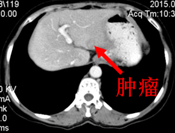

术后CT(9月)图像:

2015-10-26行CT定位下左肝占位碘125放射粒子植入术。